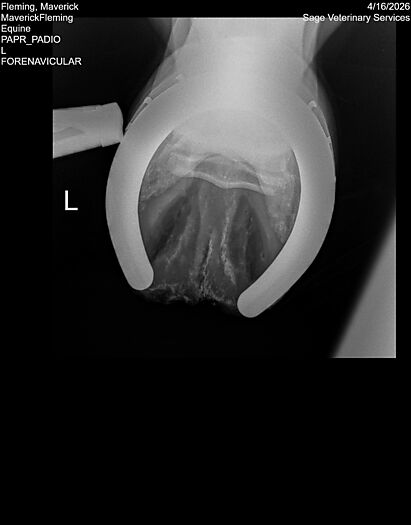

**Maverick sells at the Colorado Horse Sale’s Best of the West Select Sale on May 30th in Castle Rock, CO - He will complete the riding & handling Sift Exam, baseline veterinary exam, and will sell with 4 total radiographs (DLPMO & Front Foot Lateral)**